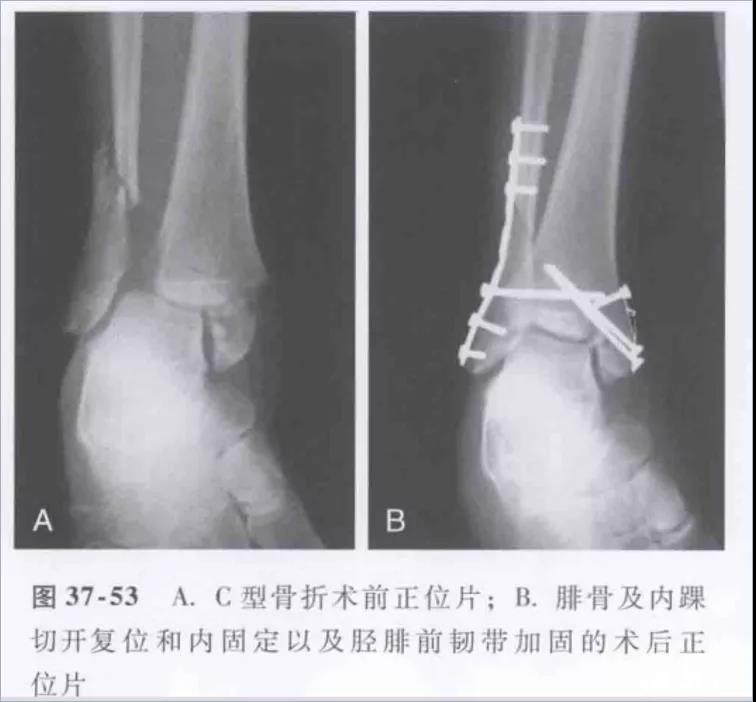

踝关节骨折分型-Weber——WeberA型-韧带下——WeberB型-经韧带——WeberC型-韧带上